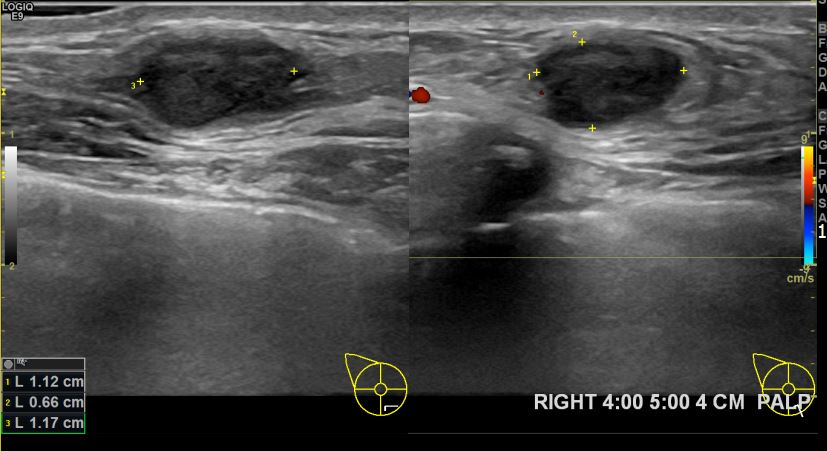

아산유외과개원후 708번째 유방암진단

상기환자 우측유방멍울만져져 내원하신 40대 여성분으로 유방암 의심혹 조직검사 시행 후 유방암 진단되었습니다.